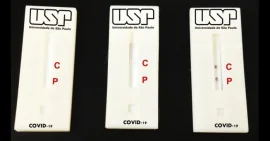

Pesquisadores desenvolvem Teste Popular de COVID-19 que amplia acesso ao diagnóstico

Pesquisadores da USP desenvolvem teste de diagnóstico de COVID-19 pela saliva

USP lança testes que ampliam capacidade de diagnóstico de COVID-19